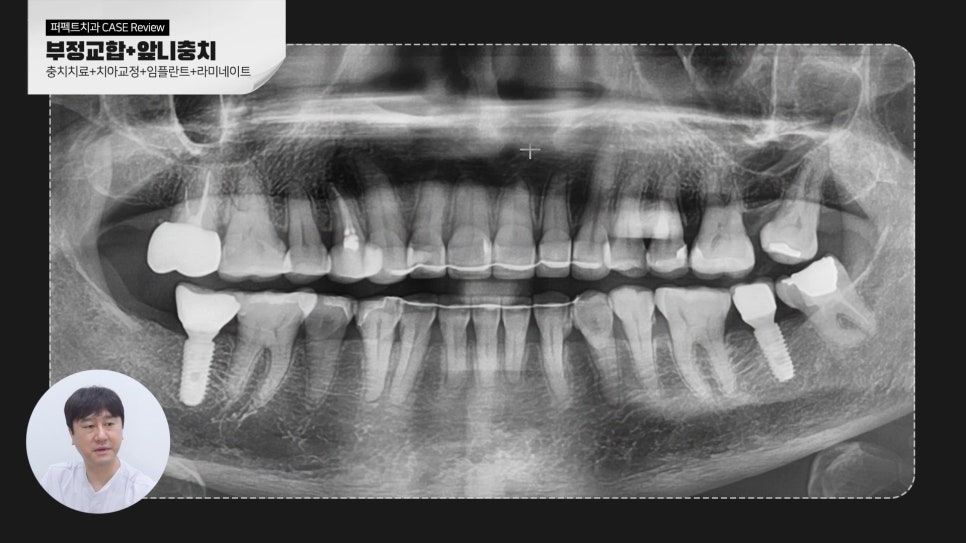

마지막 마무리 x-ray 사진을 보시면 임플란트 보철도 마무리가 되었고,

교정치료도 마무리가 되어 치열이 가지런해지고 유지장치도 부착하였습니다.

윗니 상악만 라미네이트를 하길 원하셔서 라미네이트 보철로 최종 마무리가 되었습니다.